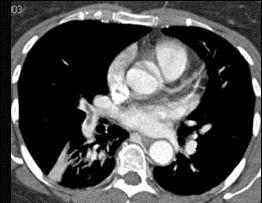

问题 男,56岁,食管癌术后,胸痛,呼吸困难,结合CT图像,最可能的诊断是 ( )

选项 A、肺水肿 B、肺不张 C、肺栓塞 D、支气管扩张 E、食管癌肺转移

答案 C